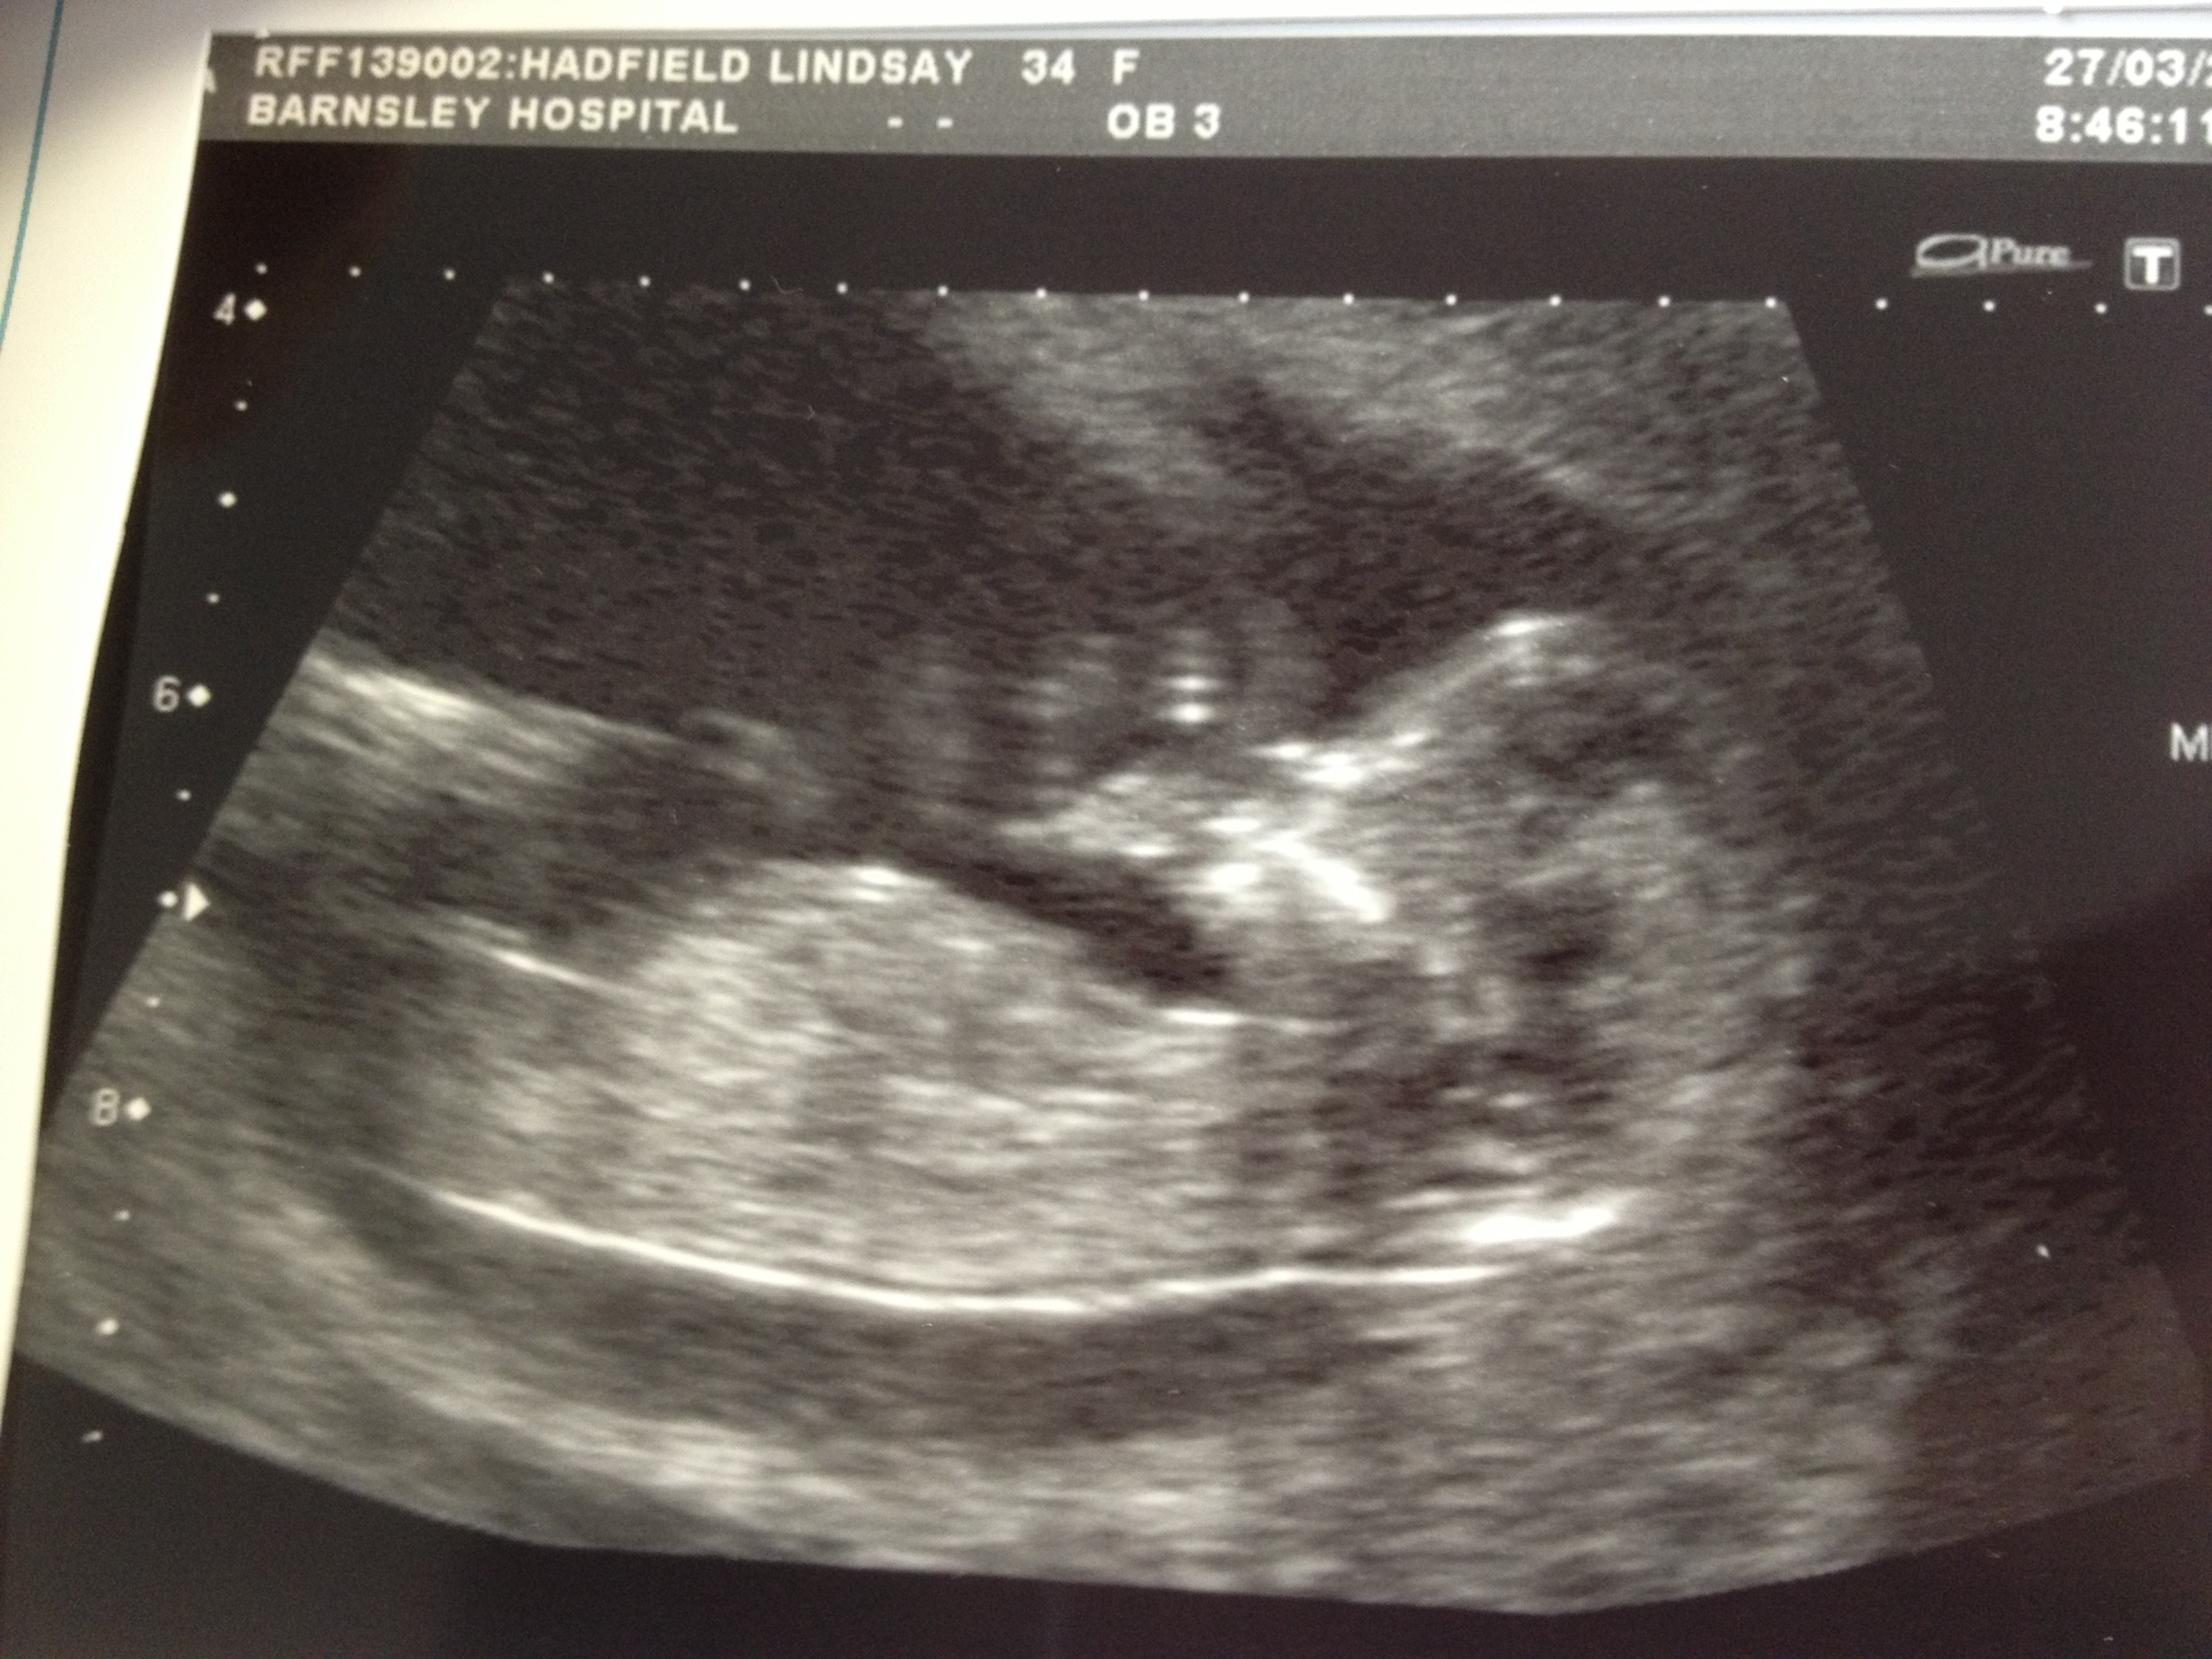

Predictions please?? 8, 11 and 13 weeks